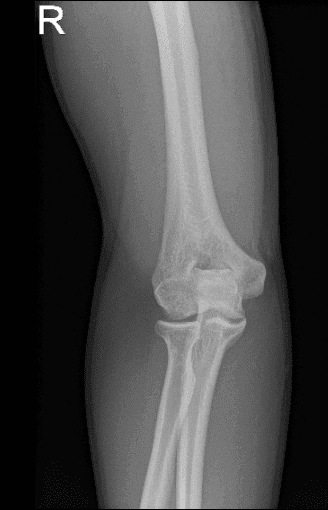

At first glance, it is suspected to have a radial head fracture. We did x-rays and found that he has a large osteophyte of the olecranon possibly secondary to chronic birth signs of the elbow.

X-ray of right elbow